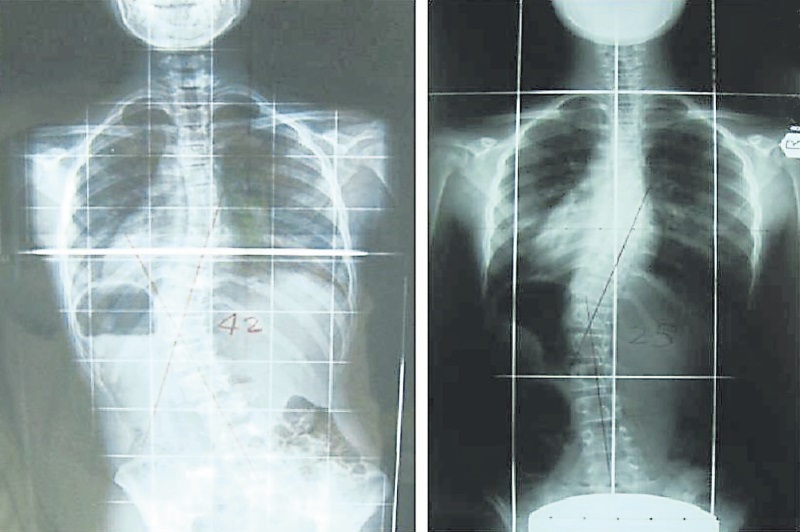

要如何鉴定脊柱侧弯?西山表示,若没有通过脊柱侧弯标准测试,一般上脊柱侧弯情况来到40至50度才会被发现,而他见过的最严重病例,是弯度达140度。

“通过这项计划,我们发现很多学生都有这问题,弯度介于20至30度之间,属于轻微侧弯,可以通过物理治疗矫正。目前我们每个星期都收到7至10名需要作进一步检查的学生名单,10个当中,有6个都是有问题,需要接受治疗,这些学生都被转介到我们医院及吉隆坡中央医院。”